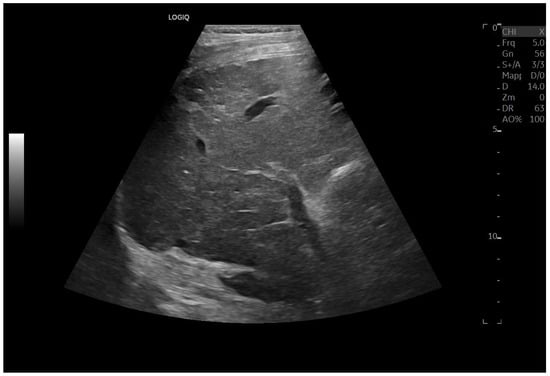

Ultrasound imaging is capable of identifying heterogeneous echotexture and hepatomegaly, which are early indicators of congestive hepatopathy [46]. Several studies have shown correlations between the extent of sonographic abnormalities and the severity of hepatic fibrosis or cirrhosis [36,47,48]. The most common ultrasound findings encompass a nodular hepatic surface, right-lobe volume reduction, smooth-to-rounded contour changes, and irregular outer profiles [49,50,51] (Figure 2). The echotexture appears granular and markedly heterogeneous, with hyperechogenic nodules of varying sizes [49,50,51] (Figure 3, Figure 4, Figure 5, Figure 6, Figure 7 and Figure 8).

Diffuse echostructural change of the left lobe with a heterogeneous hyperechoic area measuring 89 × 81 mm.